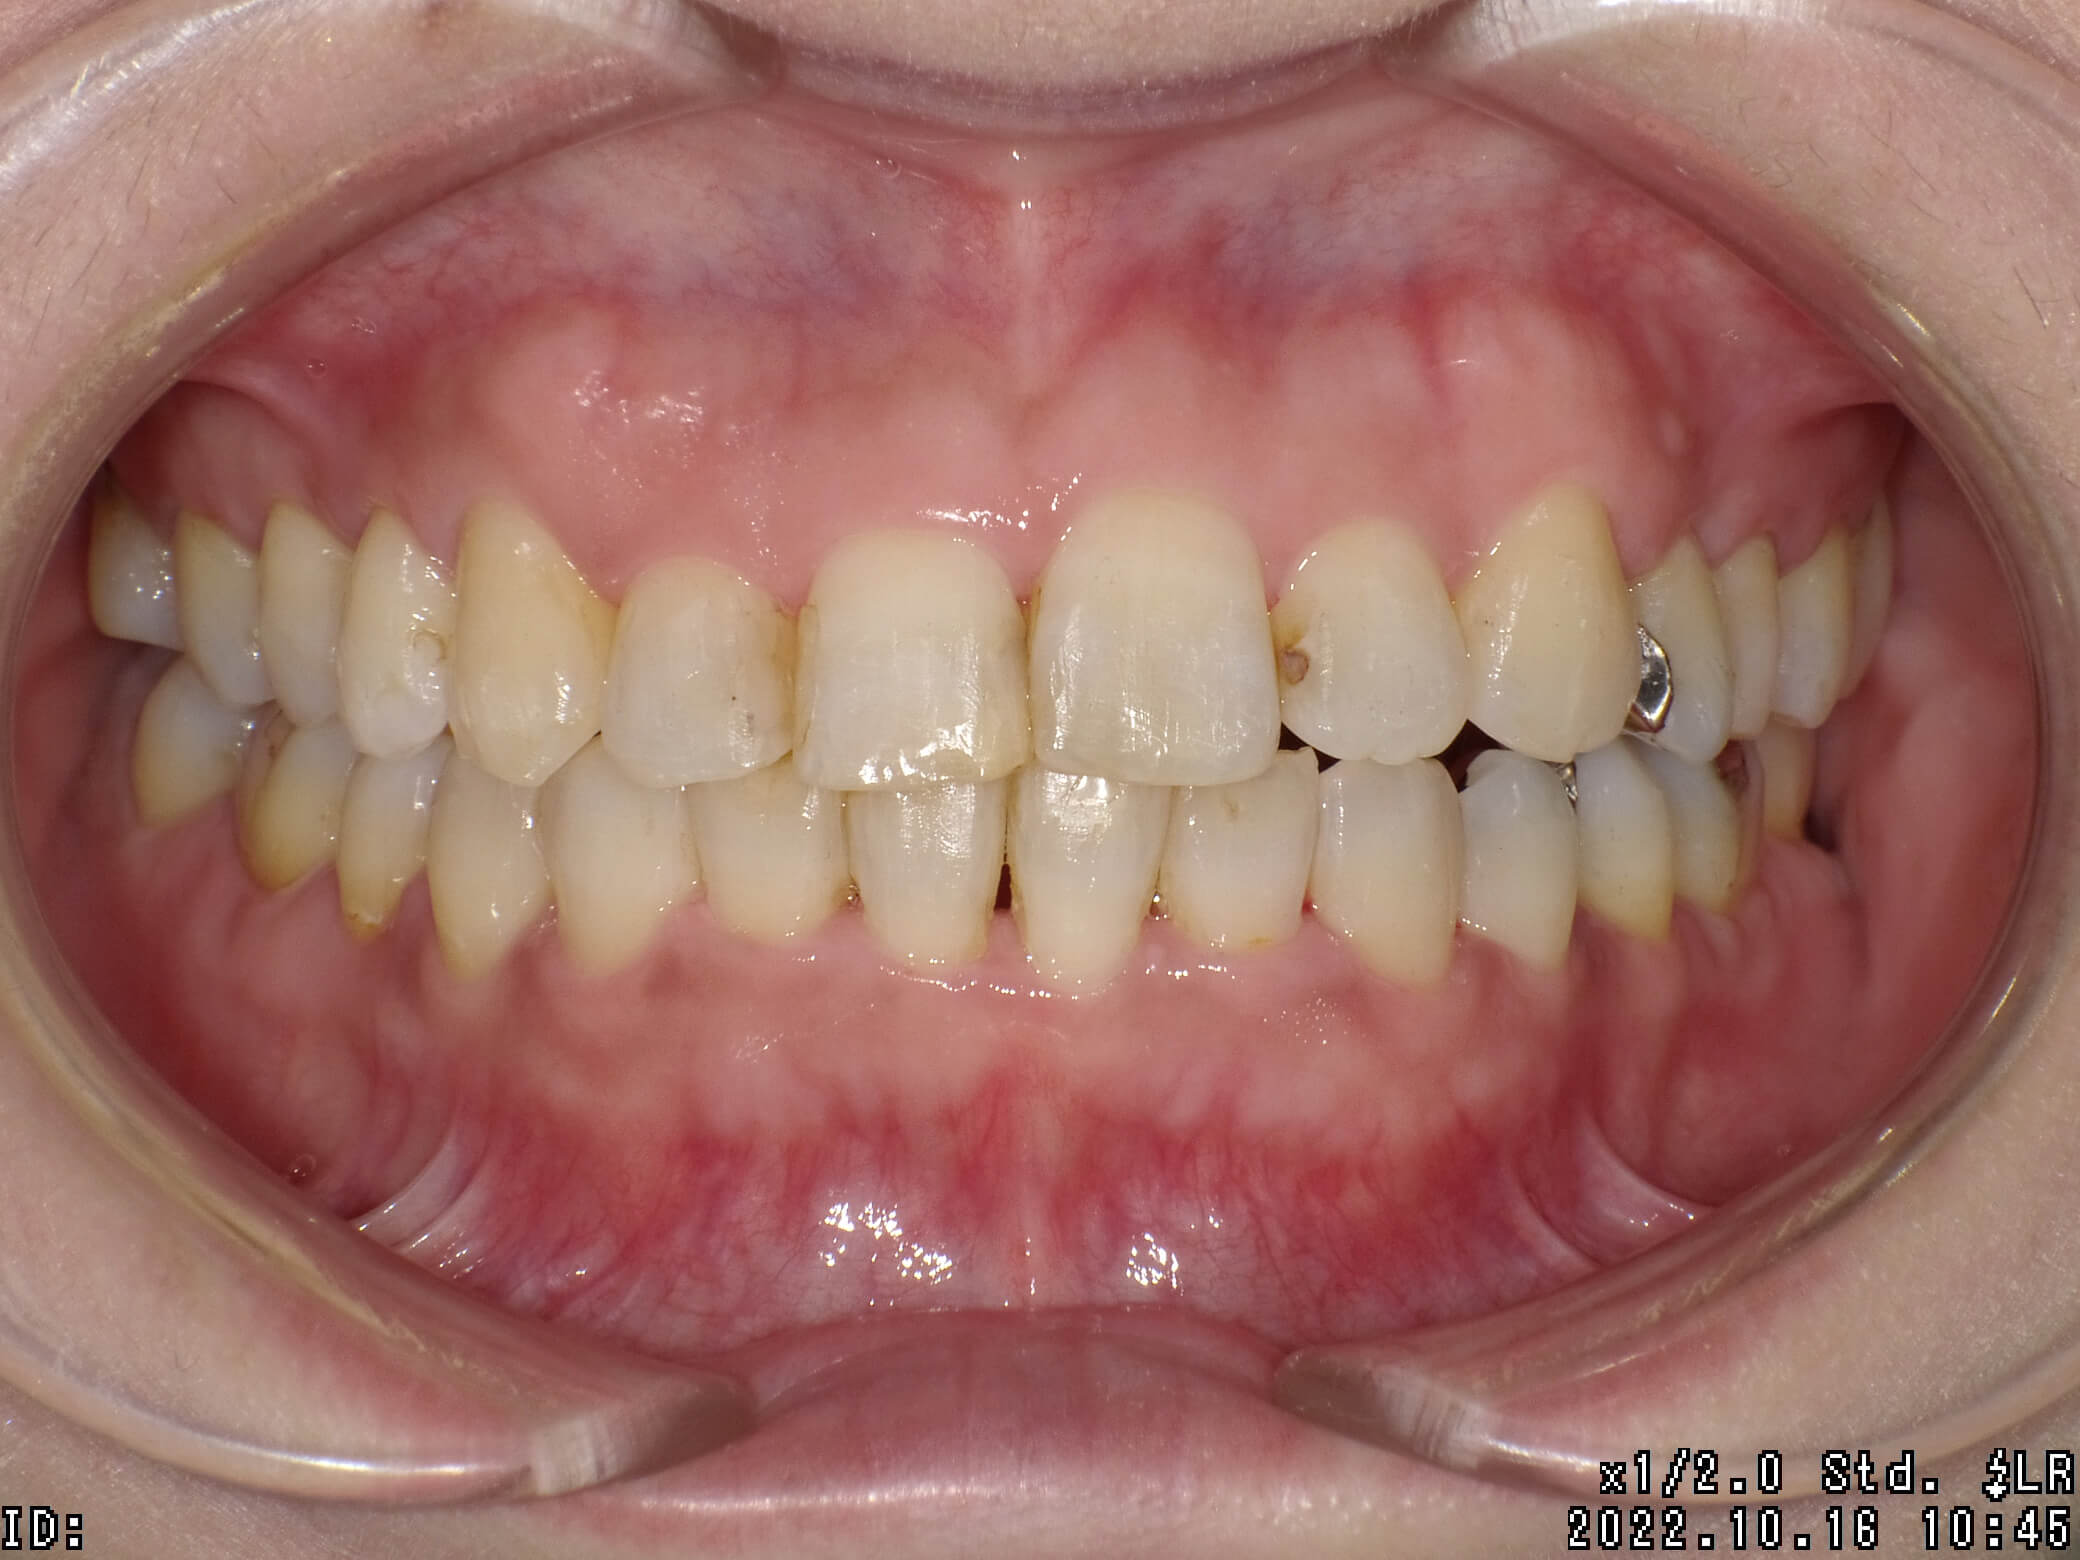

| 治療期間 | 2021年4月18日 〜2022年10月16日 |

|---|---|

| 治療費用 | 約770,000円 |

| 抜歯有無 | 抜歯あり |

| 矯正箇所 | クリアブラケット矯正 |